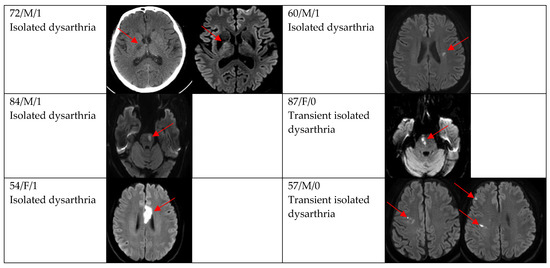

| DWI positivity | 12 (66.7) | 29 (87.9) | 0.154 |

| Single and small lesion | 10 (83.3) | 16 (55.2) | |

| Multiple or territorial lesions | 2 (16.7) | 13 (44.8) | |